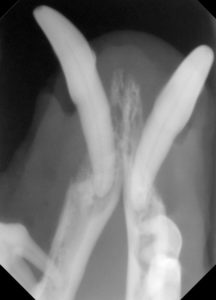

3.レントゲンでは、顎の骨が歯周病により骨折しやすい状態が確認されます。

4.下顎の顎先の骨も薄い状態です。

5.下顎の骨が溶けて、骨折しやすくなっています。

このように歯周病が進行すると、歯だけの問題でなく顎の骨が溶けてしまうため、顔の骨の骨折リスクが高くなり、治療にも慎重な歯科処置が必要になります。